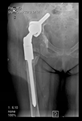

The direction of the cup stem was determined by the guide wire. The aiming device was needed to introduce this wire. After removing the aiming device, the next step was the drilling. Since a cannulated drill bit was used, the previously installed wire could guide the process. A self-positioning reaming tool was then used in the drilled channel. In the prepared cavity, the cup was fitted perfectly. Of the two stemmed cups available to us, the McMinn cup (Waldemar Link, Hamburg, Germany) had the simpler geometry and was therefore chosen. The stemmed cup was inserted according to the manufacturer’s recommendation. In the presence of a significant bone defect, a synthetic bone graft may be impacted for substitution.

The radiological examination allowed us to verify the close bone-to-implant contact and the unchanged position of the implant during follow-up.

In all the cases operated with the above-described targeting procedure, the stems of the cups remained between the cortical bone surfaces without perforation of the linea terminalis, as shown by postoperative radiographs. There were no complicated surgical situations. In 16 cases, the wound healings were uneventful, and the hips were able to bear weight again after postoperative rehabilitation.